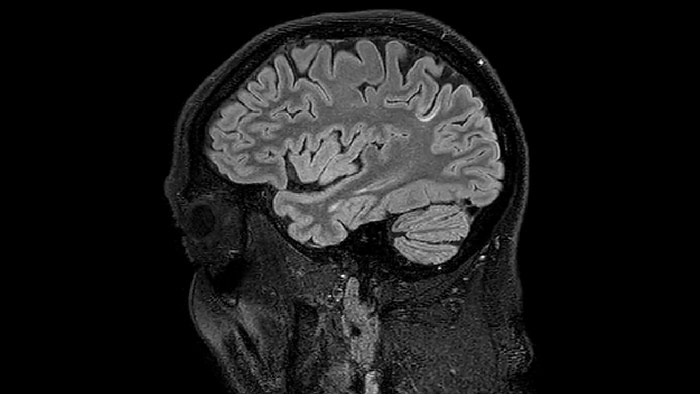

Myelin water imaging (MWI) is a breakthrough technique that was pioneered at UBC for measuring myelin content in the brain, in vivo. “Because the T2 time of water in myelin is much shorter than the T2 of water in the intraand extracellular spaces, we can separate out the myelin water signal.”

The techniques for measuring myelin have changed a lot over the years. “Since we are using the Elition, our myelin water images are much better. We're now acquiring 1 x 2 x 5 mm voxels and displaying at 1 x 1 x 2.5 mm. For a whole brain we can now measure the fraction of water in the myelin component in only about five or six minutes,” Dr. MacKay says.

Dr. Rauscher says, “For MWI we perform 3D T2 with 32 or more echoes. This used to take a long time, but with Compressed SENSE we can decrease this to ten minutes for the whole head. Because of the large field of view (FOV) on the readout direction, we even get information from the brainstem, which we previously missed when we were using the GRASE approach. Having the whole head scan is nice because it has spatial resolution, orientation and FOV that are comparable to the standard 3D clinical MS scans, including the FLAIR and 3D T2, and a 3D T1 for brain volume.”